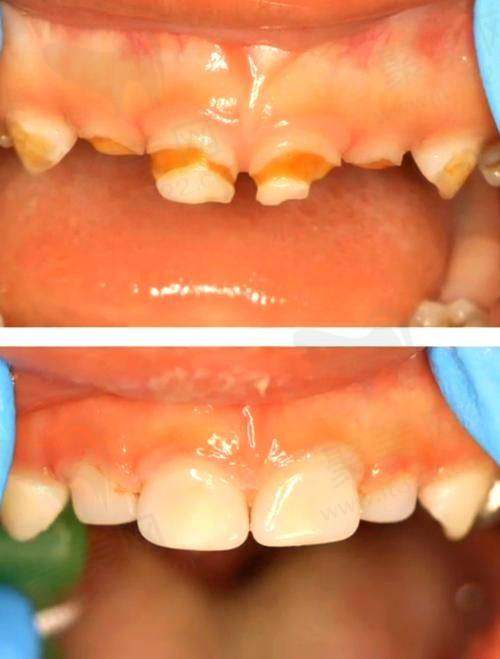

乳牙预成冠是一种专为儿童设计的牙齿修复方式,它可以有效地覆盖和保护因龋齿或其他原因而受损的乳牙。通常由不锈钢或透明塑料制成,提供一种经济且实用的解决方案,帮助儿童维护口腔健康。此类冠套修复的一个显著特点是,预成冠能够在孩子们的乳牙生长过程中提供保护,同时确保恒牙的正常发育。

与预约充填等传统补牙方式相比,乳牙预成冠的优势在于它们的固定性和持久性。因为预成冠是专门为患者的牙齿结构预先制造的,可以与牙齿实现良好的紧密结合,减少修复后牙齿再次龋坏的概率。

这项技术特别适合于那些龋齿重度的儿童,通过专精的牙科诊疗,医生会根据儿童具体的口腔状况来决定是否使用预成冠进行修复,确保成效的至佳化。

考虑一下实例:一位7岁的儿童因未及时处理的龋齿,导致乳磨牙重度受损。医生为该儿童选择了乳牙预成冠修复,成功地覆盖了受损部位,既防止了龋齿扩展,又确保了后续恒牙的正常生长。